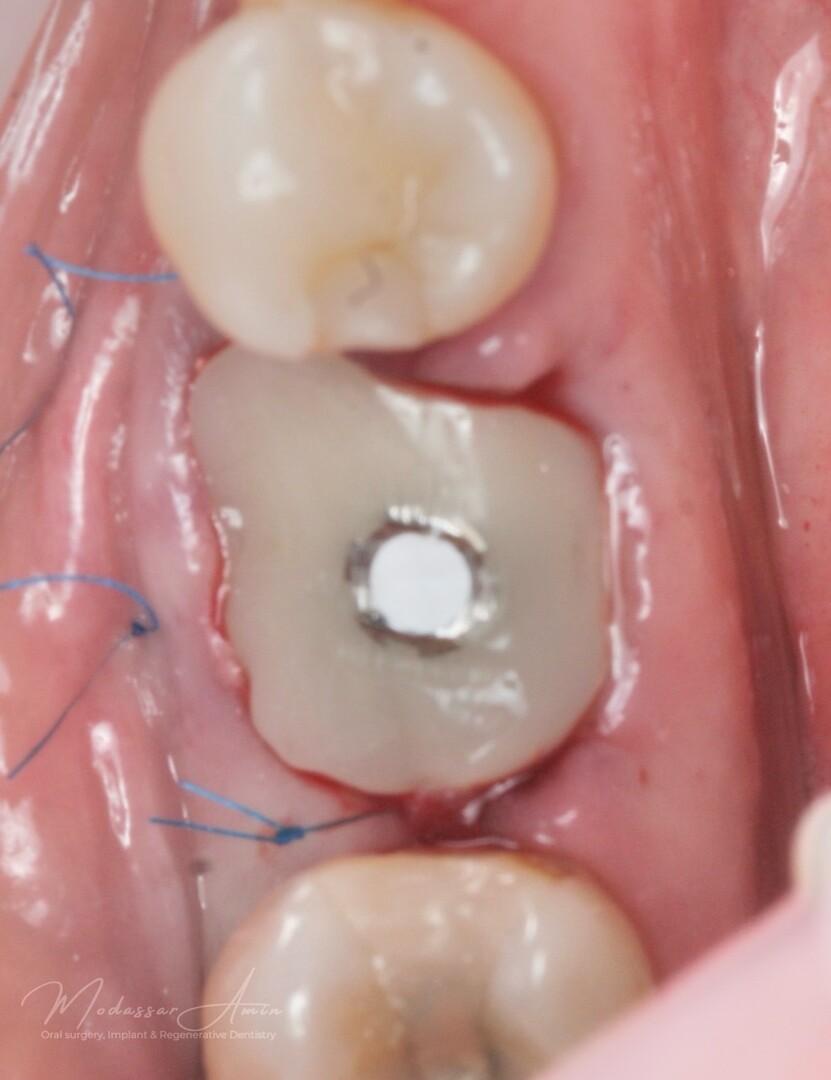

Pasienten presenterte med tann 46 som ikke kunne bevares grunnet en dyptgående infraksjon inn i furkasjonen. Forholdene lå til rette for en immediate implantatbehandling. Ved hjelp av Versah osseodensifikasjonsbor ble det interradikulære beinet ekspandert på en skånsom og forutsigbar måte, noe som ga høy primærstabilitet (>40 Ncm) til tross for en lokal bendefekt apikalt mesialt etter kronisk apikal periodontitt. Den gode stabiliteten muliggjorde bruk av SSA (Sealing Socket Abutment) for forsegling. På grunn av tynn bløtvevsfenotype bukkalt ble behandlingen supplert med bindevevstransplantat (CTG):

SSA (Sealing Socket Abutment) + CTG (bindevevsgraft)